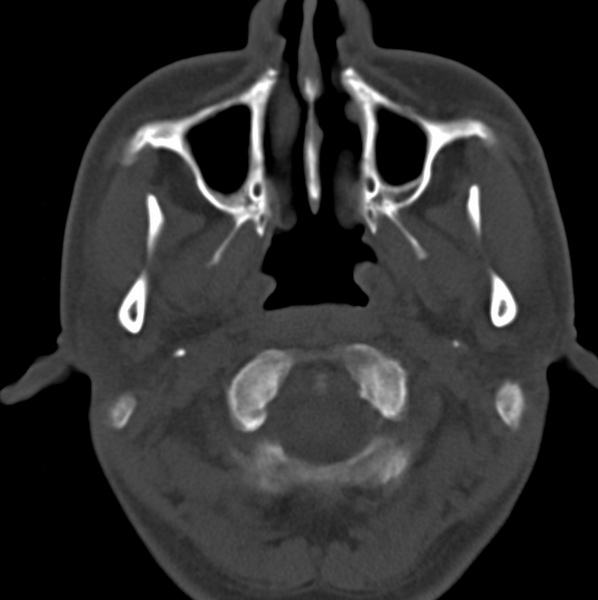

男、31、鼻咽部肿瘤放疗后请帮忙看看。

效果好,右侧破裂孔扩大,局部骨质缺损,为颅底骨质破坏。

1)鼻咽部肿瘤侵犯颅底放疗术后改变。2)左侧蝶窦炎。

咽后壁增厚,左侧咽鼓管隆突增大、咽鼓管咽口变浅,同侧咽旁间隙较窄。右侧颅底骨质破坏?为什么不在同一侧?

鼻咽部肿瘤侵犯颅底放疗术后改变.